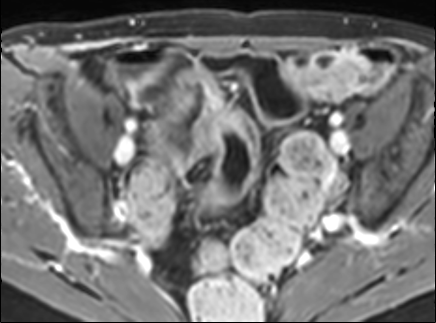

Bệnh nhân nữ 48 tuổi, đang điều trị bằng thuốc kháng TNF, được chỉ định nội soi đại tràng.

Phát hiện hẹp lòng ruột ở đại tràng sigma, không thể vượt qua được khi nội soi.

MR-enterography được thực hiện để đánh giá mức độ lan rộng của chỗ hẹp.

Cuộn qua các hình ảnh.

Ruột non bình thường, nhưng ghi nhận các đoạn hẹp ở đại tràng xuống và đại tràng ngang.

Cả hai đoạn hẹp đều có thành ruột dày đến 8 mm và ngấm thuốc rõ rệt theo kiểu niêm mạc ở đại tràng xuống và kiểu phân lớp ở đại tràng ngang.

Giãn ruột trước chỗ hẹp được ghi nhận ở cả hai đoạn.

Do các chỗ hẹp này không hiện diện khi nội soi đại tràng trước khi điều trị kháng TNF, nhiều khả năng chúng đã hình thành trong quá trình điều trị.

Do đó, quyết định phẫu thuật cắt đại tràng gần toàn bộ với miệng nối hồi-sigma đã được đưa ra.